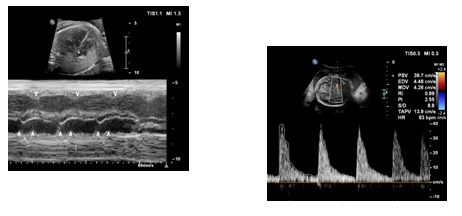

Ciężarna w 31 tygodniu ciąży została skierowana na badanie echokardiograficzne płodu z powodu nieregularnej czynności serca płodu widocznej w badaniu ultrasonograficznym. Na podstawie badania M-mode tego płodu rozpoznać należy:

Ciężarna 30-letnia, wywiad rodzinny nieobciążony, została skierowana na badanie echokardiograficzne w 24 tygodniu ciąży z powodu bradykardii 70 ud/min. Obraz M-mode oraz przepływ w tętnicy środkowej mózgu u tego płodu przedstawiono poniżej. Wskaż stwierdzenie prawdziwe dotyczące opisanego przypadku: